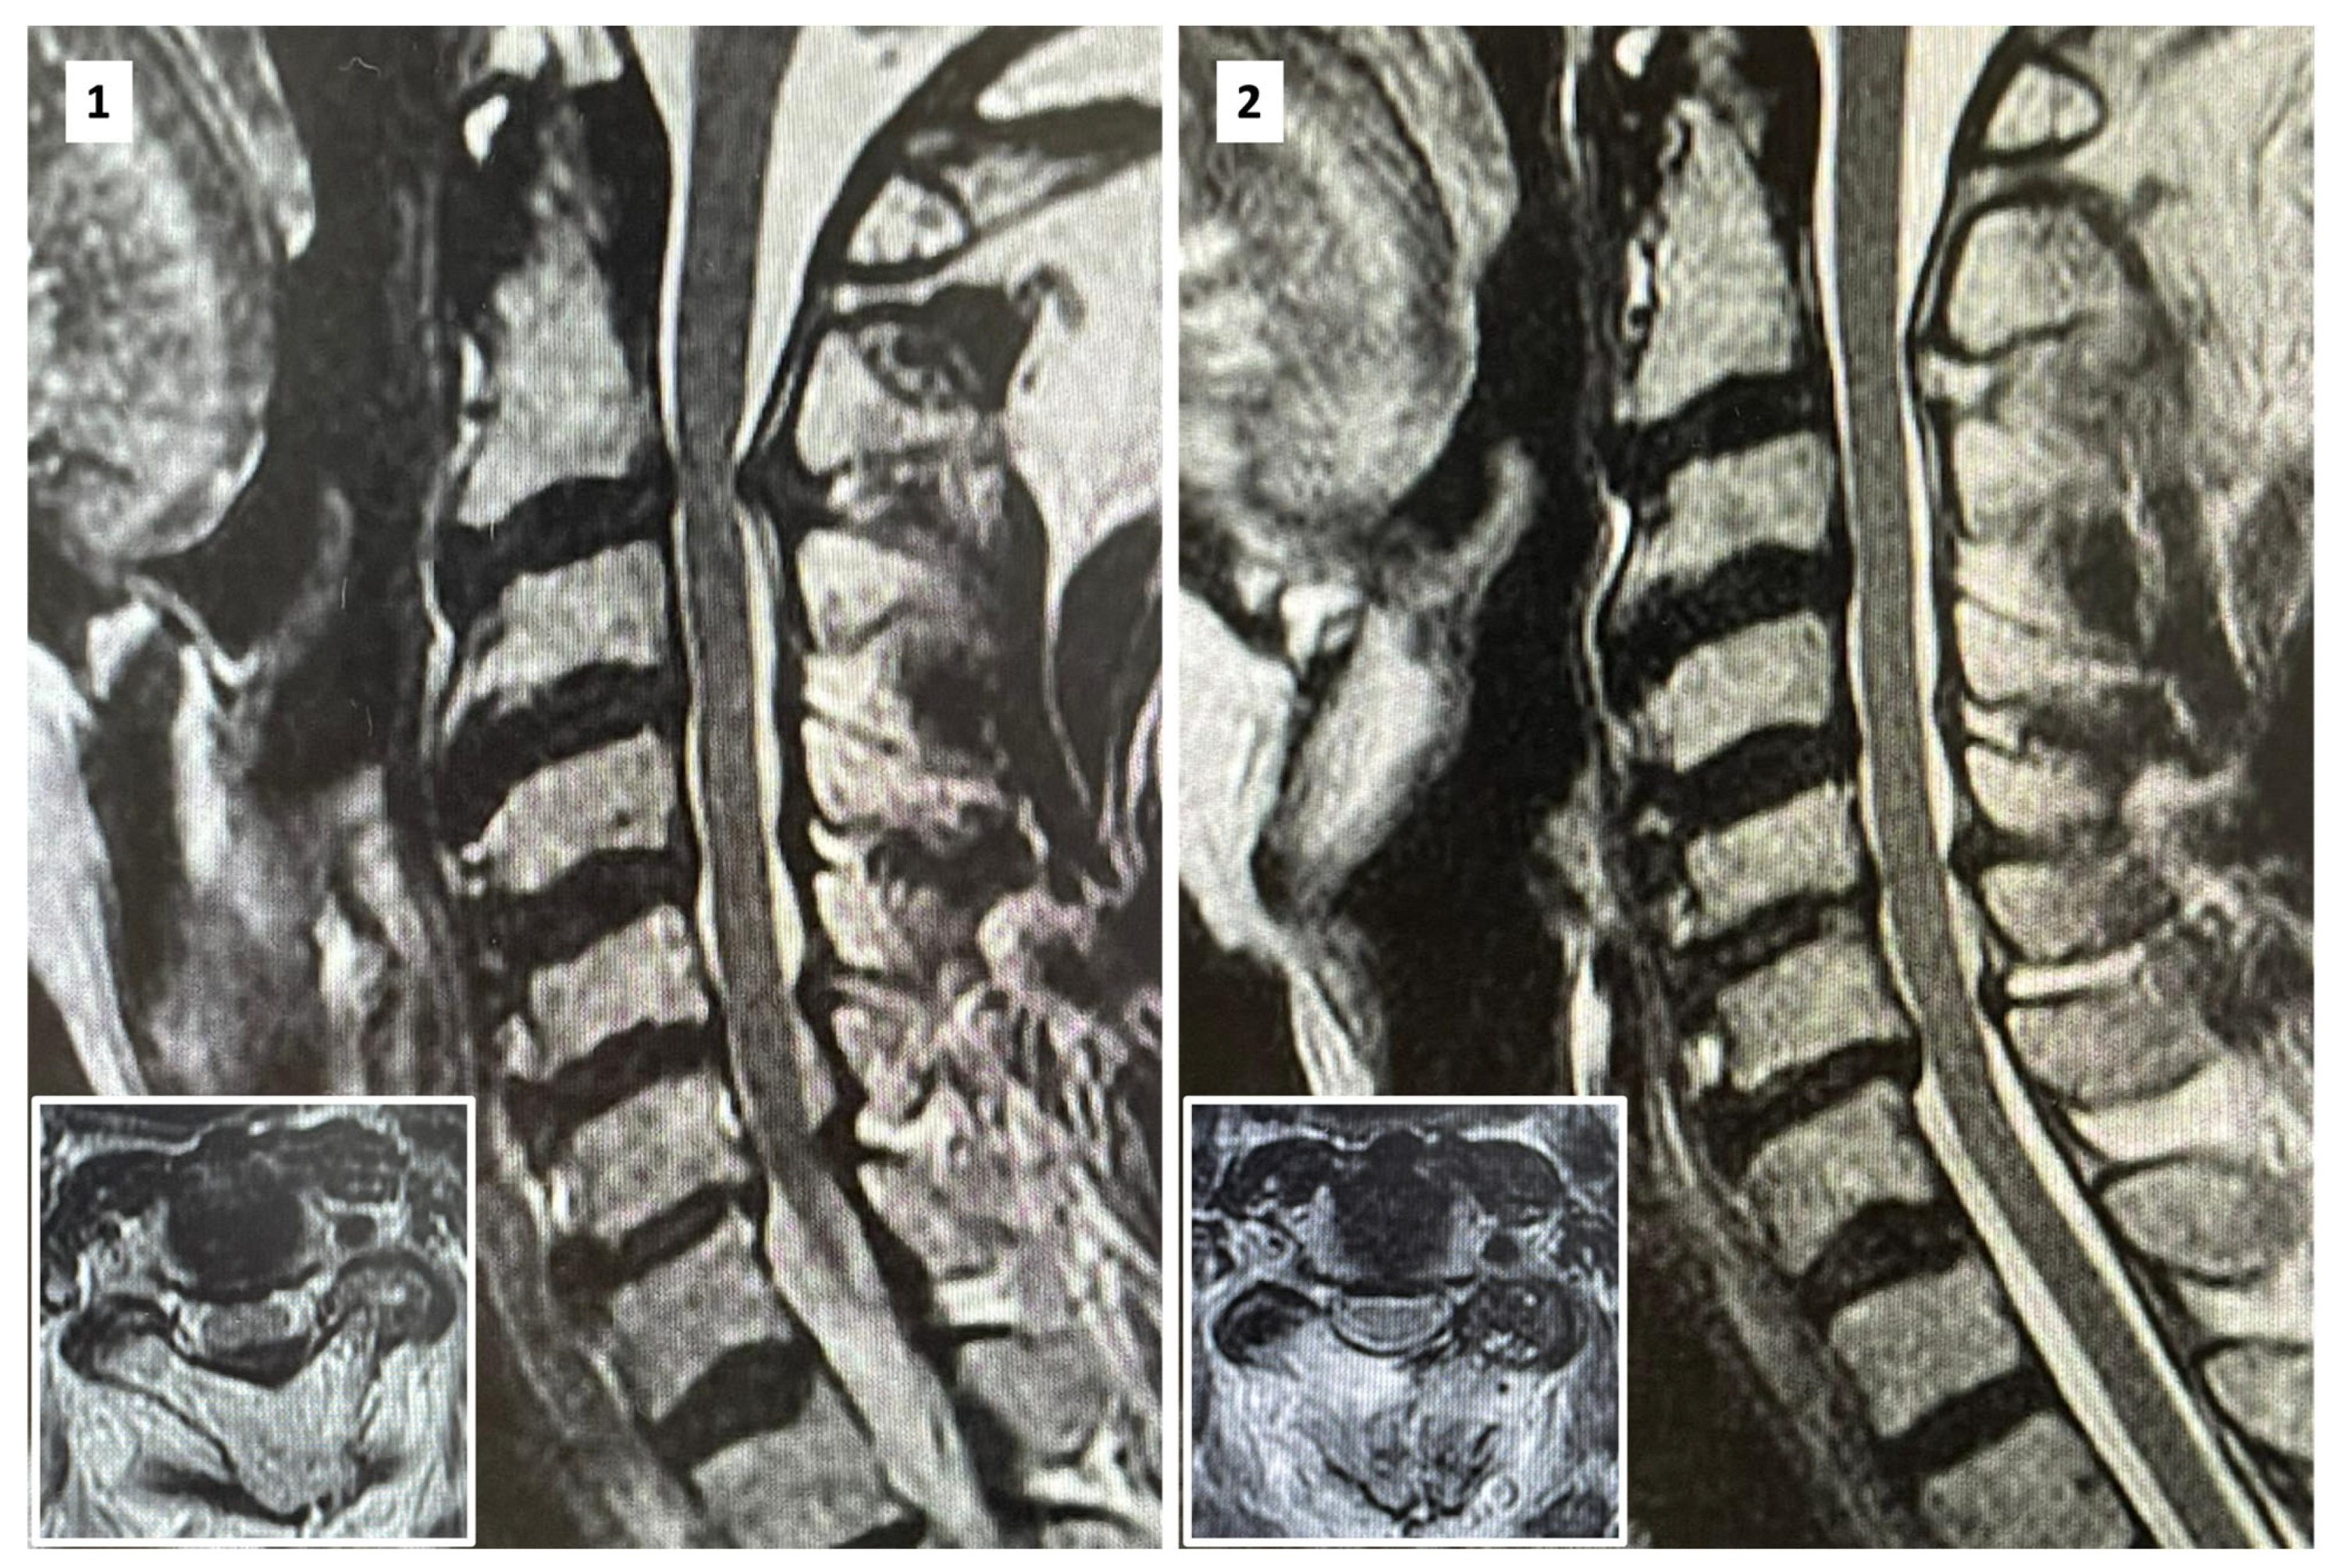

2. Surgical Technique